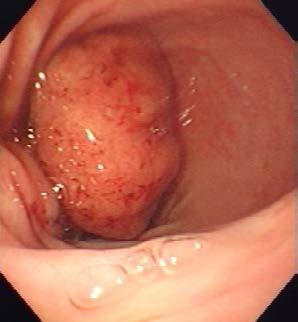

The cat was treated with Itraconazole 50mg SID and topically with Otoflush (Dermcare-Vet) and silver sulfadiazine ointment (Flamazine, Smith and Nephew). At recheck two weeks later, she had shown a 20% improvement with the skin remaining erythematous with some reduction in ulceration and minimal change in the subcutaneous nodules. She was changed to Fluconazole 50mg BID. At recheck another four weeks later, she had shown marked improvement as evident

in the image below (Figure 3). There were still multiple palpable nodular lesions in the subcutis but these had significantly reduced in size since the last visit (estimated 70% reduction) and there was one 8mm ulcer. Numerous Cryptococcus organisms were evident on FNA of a nodule and on a scraping of the ulcer. A liver profile biochemistry panel was normal with albumin 28.4g/L (RI 27-40). She was continued on Fluconazole 50mg BID with a plan to recheck in 8 weeks.